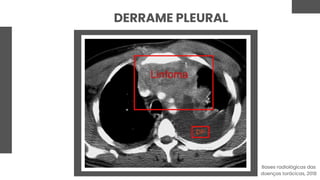

DERRAME PLEURAL

Acúmulo anormal de líquido entre

as pleuras

A imagem aparece como uma

opacidade na região de acúmulo

de líquido

Transudato, exsudato, sangue, linfa,

entre outros

Os transudatos estão mais

associados à insuficiência

cardíaca congestiva e estados de

hipoproteinemia

D: derrame e espessamento pericárdico

P: derrame pleural bilateral

Bases radiológicas das doenças torácicas, 2018

Exsudatos decorrem de inflamação

ou alteração de drenagem linfática

- mais encontrados nos quadros

infecciosos (mais de 50% das

pneumonias) e neoplasias

A TC é efetiva na demonstração do

tamanho, distribuição, extensão e

lesões associadas ao derrame

pleural

Bases radiológicas das

doenças torácicas, 2018